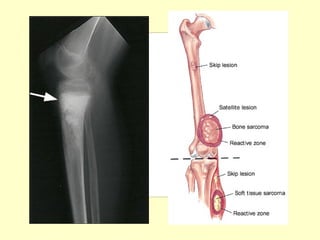

• Si el t. Es de rapido crecimiento va a

• En cambio en los t. De crecimiento lento se

produce un “balonamiento” de la cortical

que puede ser normal o fina